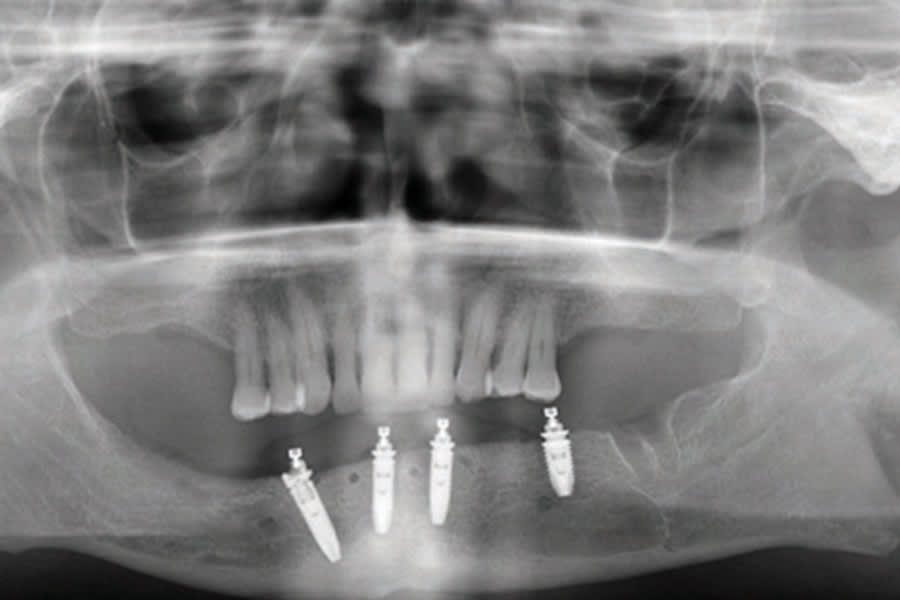

A 58-year-old male patient presented with a complaint of mobile teeth on the lower right, seeking a more stable situation. The patient was wearing a mandibular partial denture and the only remaining teeth on the lower arch was the left second molar (No. 18), as well as the first and second premolars bilaterally. An intraoral exam noted mobility on teeth Nos. 28 and 29. The patient was missing all maxillary molars, and the remaining maxillary dentition was stable periodontally. A panoramic radiograph was taken to evaluate the dentition and associated anatomy (Figure 1). Radiographically, significant bone loss was noted on the right mandibular premolars.

The intraoral scans were imported into DTX Studio software (DEXIS) to begin the implant and prosthesis planning (Figures 2 and 3). A virtual prosthesis was designed to articulate with the maxillary dentition (Figure 3). Implants were planned at four sites in the mandibular arch (Figure 1).